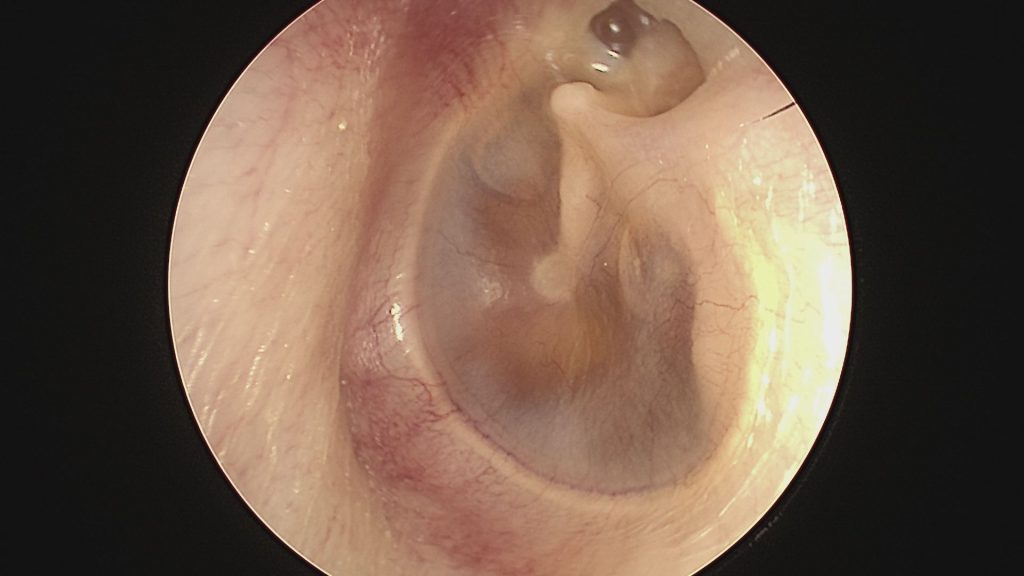

La perforazione del timpano visibile all’otoscopia è un segno distintivo dell’otite suppurativa cronica. Senza trattamento, questi sintomi tendono a peggiorare nel tempo.

La diagnosi di otite costante inizia con un esame otoscopico accurato per valutare perforazione timpanica e presenza di secrezioni. Il medico controlla lo stato della mucosa e cerca segni di colesteatoma.